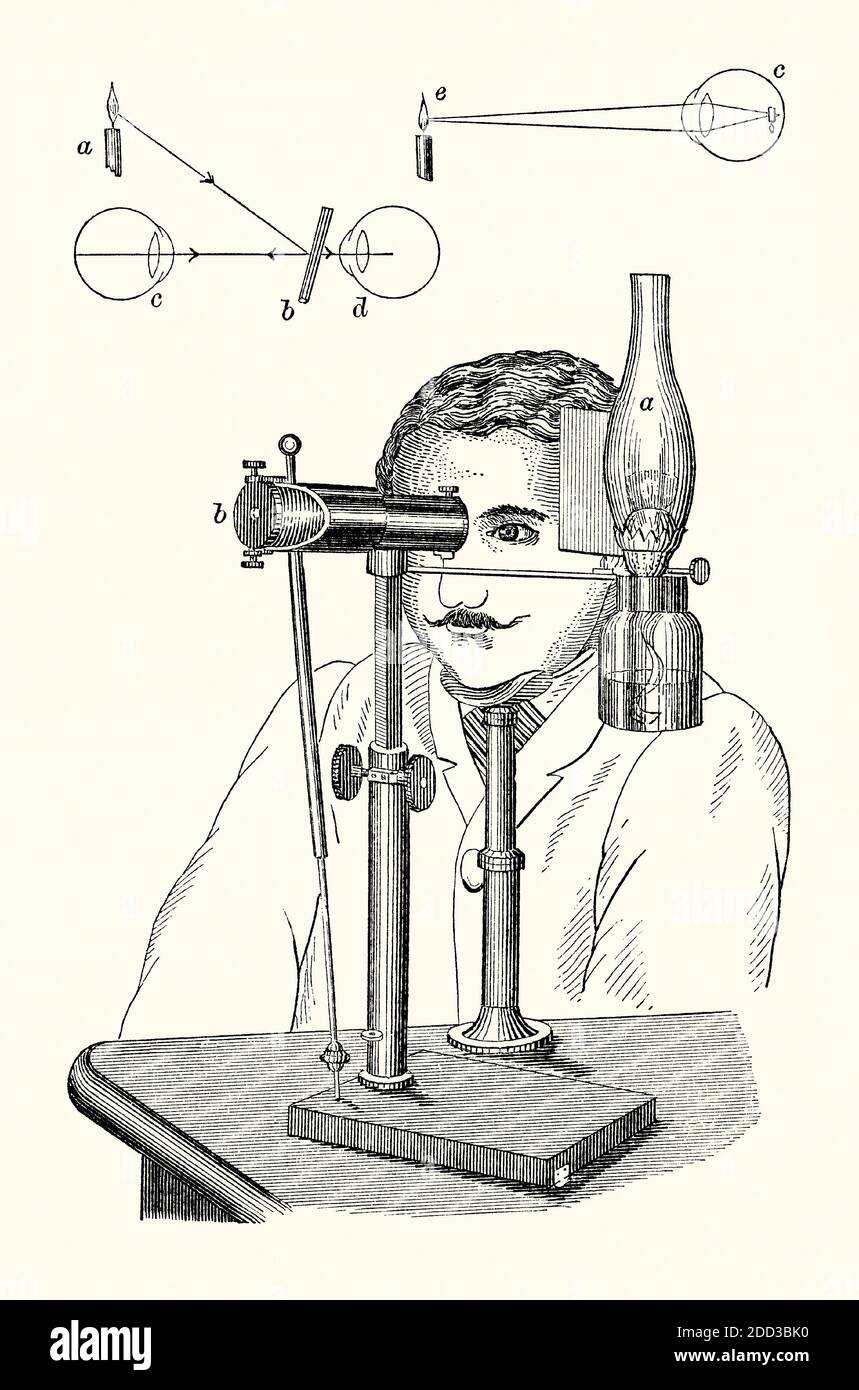

An old engraving of an ophthalmoscope. It is from a Victorian book of the 1880s. Ophthalmoscopy (or funduscopy) allows a doctor to see inside the eye using this device. This version is Knapp’s auto-ophthalmoscope, set up in front of a patient. A light source (a) supplies light to an inclined reflector (b) which bounces the light towards the patient’s pupil (c in the top diagram). A hole in the plate at the rear of the instrument allows the doctor to view (d). The ophthalmoscope was invented by Hermann von Helmholtz in 1851. Hermann Knapp of New York was an expert instrument and lens maker. Stock Photohttps://www.alamy.com/image-license-details/?v=1https://www.alamy.com/an-old-engraving-of-an-ophthalmoscope-it-is-from-a-victorian-book-of-the-1880s-ophthalmoscopy-or-funduscopy-allows-a-doctor-to-see-inside-the-eye-using-this-device-this-version-is-knapps-auto-ophthalmoscope-set-up-in-front-of-a-patient-a-light-source-a-supplies-light-to-an-inclined-reflector-b-which-bounces-the-light-towards-the-patients-pupil-c-in-the-top-diagram-a-hole-in-the-plate-at-the-rear-of-the-instrument-allows-the-doctor-to-view-d-the-ophthalmoscope-was-invented-by-hermann-von-helmholtz-in-1851-hermann-knapp-of-new-york-was-an-expert-instrument-and-lens-maker-image386693636.html

An old engraving of an ophthalmoscope. It is from a Victorian book of the 1880s. Ophthalmoscopy (or funduscopy) allows a doctor to see inside the eye using this device. This version is Knapp’s auto-ophthalmoscope, set up in front of a patient. A light source (a) supplies light to an inclined reflector (b) which bounces the light towards the patient’s pupil (c in the top diagram). A hole in the plate at the rear of the instrument allows the doctor to view (d). The ophthalmoscope was invented by Hermann von Helmholtz in 1851. Hermann Knapp of New York was an expert instrument and lens maker. Stock Photohttps://www.alamy.com/image-license-details/?v=1https://www.alamy.com/an-old-engraving-of-an-ophthalmoscope-it-is-from-a-victorian-book-of-the-1880s-ophthalmoscopy-or-funduscopy-allows-a-doctor-to-see-inside-the-eye-using-this-device-this-version-is-knapps-auto-ophthalmoscope-set-up-in-front-of-a-patient-a-light-source-a-supplies-light-to-an-inclined-reflector-b-which-bounces-the-light-towards-the-patients-pupil-c-in-the-top-diagram-a-hole-in-the-plate-at-the-rear-of-the-instrument-allows-the-doctor-to-view-d-the-ophthalmoscope-was-invented-by-hermann-von-helmholtz-in-1851-hermann-knapp-of-new-york-was-an-expert-instrument-and-lens-maker-image386693636.htmlRM2DD3BK0–An old engraving of an ophthalmoscope. It is from a Victorian book of the 1880s. Ophthalmoscopy (or funduscopy) allows a doctor to see inside the eye using this device. This version is Knapp’s auto-ophthalmoscope, set up in front of a patient. A light source (a) supplies light to an inclined reflector (b) which bounces the light towards the patient’s pupil (c in the top diagram). A hole in the plate at the rear of the instrument allows the doctor to view (d). The ophthalmoscope was invented by Hermann von Helmholtz in 1851. Hermann Knapp of New York was an expert instrument and lens maker.